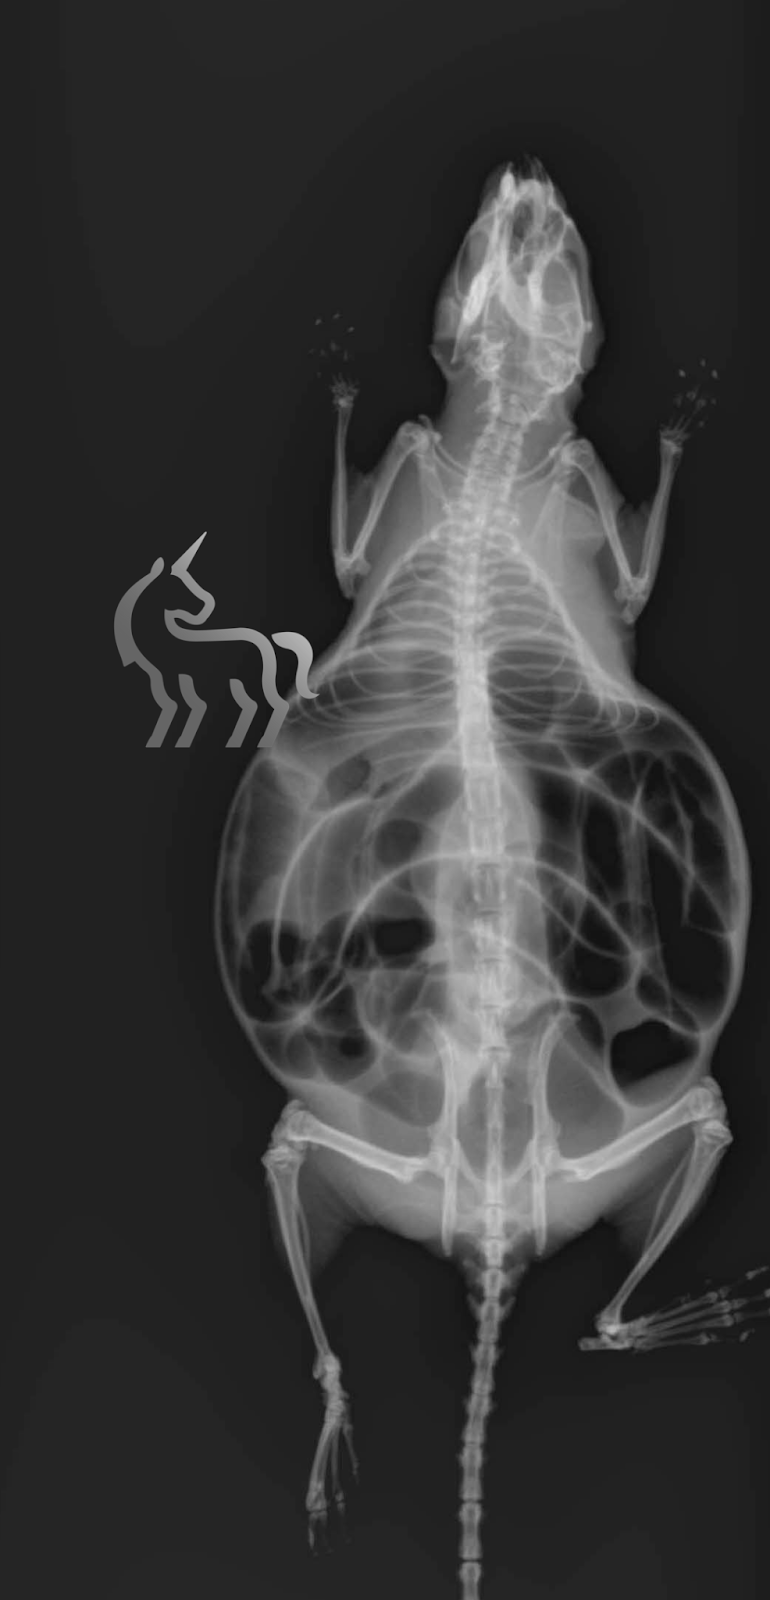

- Ballonnement abdominal : Un gonflement important de l’abdomen dû à l’accumulation d’air et de matières non évacuées.

Le mégacolon chez le rat : Une origine génétique

Les symptômes du mégacôlon